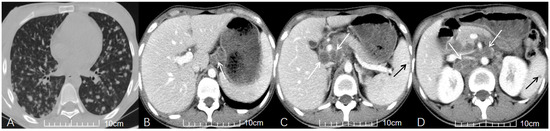

Cover Story (view full-size image): This study analyzes the prevalence and clinical relevance of incidental findings from 683 chest CT scans performed for suspected COVID-19 over nearly two years. Using the COVID-19 Pneumonia Imaging Classification and a structured relevance scale, we evaluated how these findings were identified, categorized, and clinically managed. Incidental findings occurred in 94 patients (13.8%), with women affected more frequently. Although most findings were of limited clinical significance, several required further diagnostics and work up. This study highlights the need for consistent follow-up and standardized management pathways to ensure that clinically significant incidental findings are appropriately addressed. View this paper

Clinical and CT Features of HIV-Negative and HIV-Positive Patients with Abdominal Tuberculous Lymphadenopathy

Background: The diagnosis of abdominal tuberculous lymphadenopathy (ATBL) remains challenging in clinical practice. Patients with ATBL and HIV infection may have atypical clinical and computed tomography (CT) features. The aim of this study was to investigate the impact of HIV infection on [...] Read more.

Background: The diagnosis of abdominal tuberculous lymphadenopathy (ATBL) remains challenging in clinical practice. Patients with ATBL and HIV infection may have atypical clinical and computed tomography (CT) features. The aim of this study was to investigate the impact of HIV infection on the clinical and CT features of ATBL patients. Methods: From January 2012 to March 2023, 178 patients with untreated ATBL were retrospectively analyzed. Patients with ATBL were classified into HIV-negative group (n = 152) and HIV-positive group (n = 26). In addition to the clinical characteristics of the patients, the features of ATBL (e.g., size and location) were evaluated via CT. The Mann–Whitney U test (for continuous variables) and Fisher’s exact test (for categorical variables) were used to compare clinical data and CT imaging features between the two groups. Missing values were handled using multiple imputation, and the Benjamini–Hochberg procedure was applied to control the false discovery rate (FDR) in multiple comparisons. Post hoc power analysis for key variables was performed. Results: Compared with the HIV-negative group, the HIV-positive group had older age, lower CD4+ T-cell counts, and larger ATBL diameter. The HIV-positive group also showed a stronger tendency for disease dissemination, with significantly higher rates of smear positivity, miliary pulmonary tuberculosis (PTB), and disseminated tuberculosis (TB). On CT imaging, the HIV-positive group had a higher frequency of ATBL involvement in the upper para-aortic region, portacaval space, and hepatogastric ligament. In contrast, abdominal distension was more common in the HIV-negative group. post hoc power analysis confirmed that most key variables had adequate statistical power (≥0.8), except for age (power = 0.597) and ATBL diameter (Power = 0.769). Conclusions: The clinical and CT features of ATBL differ significantly between HIV-negative and HIV-positive patients. Full article

(This article belongs to the Section Medical Imaging and Theranostics)

Show Figures

Figure 1